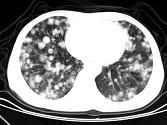

问题 男,42岁,肝区痛1月余,最近2周咯血丝痰,胸部CT如图,最可能的诊断为 ( )

选项 A.葡萄球菌肺炎 B.过敏性肺炎 C.结节病 D.肺转移瘤 E.韦格肉芽肿

答案 D